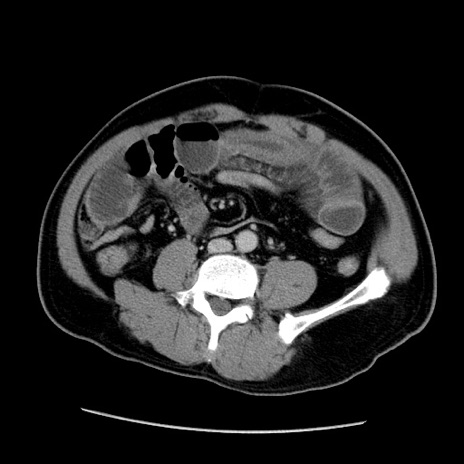

症例22(横断像)

【症例】50歳代男性

【主訴】腹痛

【現病歴】AVMからの被殻出血のため回復期リハ病棟入院中。 本日午後3時頃急に下腹部痛が出現した。

【既往歴】AVM、被殻出血、虫垂炎、高血圧

【身体所見】意識晴明、左半身不全麻痺、会話の理解は良好、36.5°C、腹部:膨隆、全体に板状硬、下腹部正中に圧痛点あり、反跳痛-、筋性防御不明、右下腹部にope scar

【データ】WBC 9400、CRP 0.06